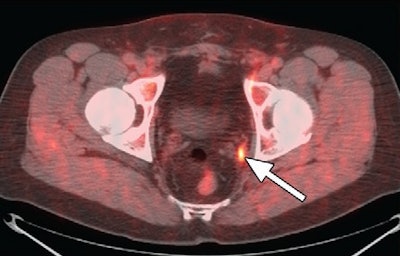

The promising results led to a grant from the U.S. National Institutes of Health, with study findings published in Radiology in 2011 (Vol. 259:3, pp. 852-861). In the study, Schuster and colleagues compared FACBC-PET/CT to SPECT/CT with indium-111 capromab pendetide (ProstaScint, Cytogen) for detecting recurrent prostate cancer.

For disease detection in the prostate bed, FACBC-PET/CT had greater sensitivity than indium-111-based SPECT/CT (89% versus 69%), along with better specificity (67% versus 58%) and better accuracy (83% versus 67%).

In the detection of extraprostatic recurrence, FACBC-PET/CT showed sensitivity of 100%, compared with only 10% for indium-111-based SPECT/CT; both modalities turned in specificity of 100%. FACBC-PET/CT had 100% accuracy, compared with 47% accuracy for SPECT/CT with indium-111.